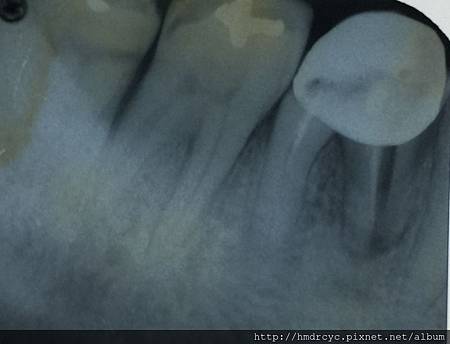

假牙必須利用X光片來更精確的判斷有沒有問題

在X光上面假牙是白色的影像

但X光片判讀困難 所以這部分必須仰賴醫師的專業

牙周病不管在假牙或自然牙齒

都必須X光來診斷嚴重程度

輕微的牙周病經過照X光片

可以檢查出牙肉底下牙結石的位置

而牙周病最可怕的部分就是造成骨頭破壞

有時候外表看起來不錯的牙齒

其實裡面骨頭以經破壞嚴重甚至造成動搖

嚴重者骨頭以經完全破壞

牙齒失去支撐 就會浮起來

這時就只能考慮拔除